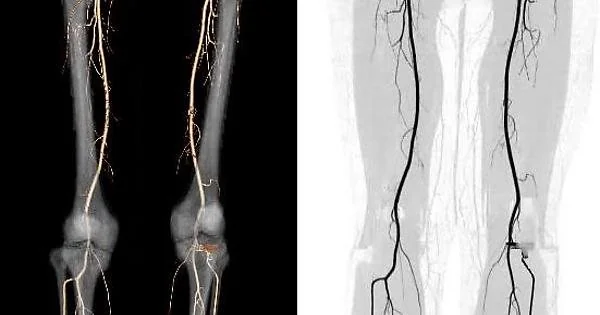

A Lower Extremity Arteriogram, also called Peripheral Angiography, is a diagnostic imaging procedure used to visualize arteries in the legs. It helps identify blockages, narrowing (stenosis), or other abnormalities in blood vessels that may be causing leg pain, non-healing wounds, or poor circulation.

The procedure uses X-ray imaging and a special contrast dye that is injected into the arteries. The dye highlights blood flow patterns, allowing Dr. Suri to see areas of restricted or blocked circulation in real-time.